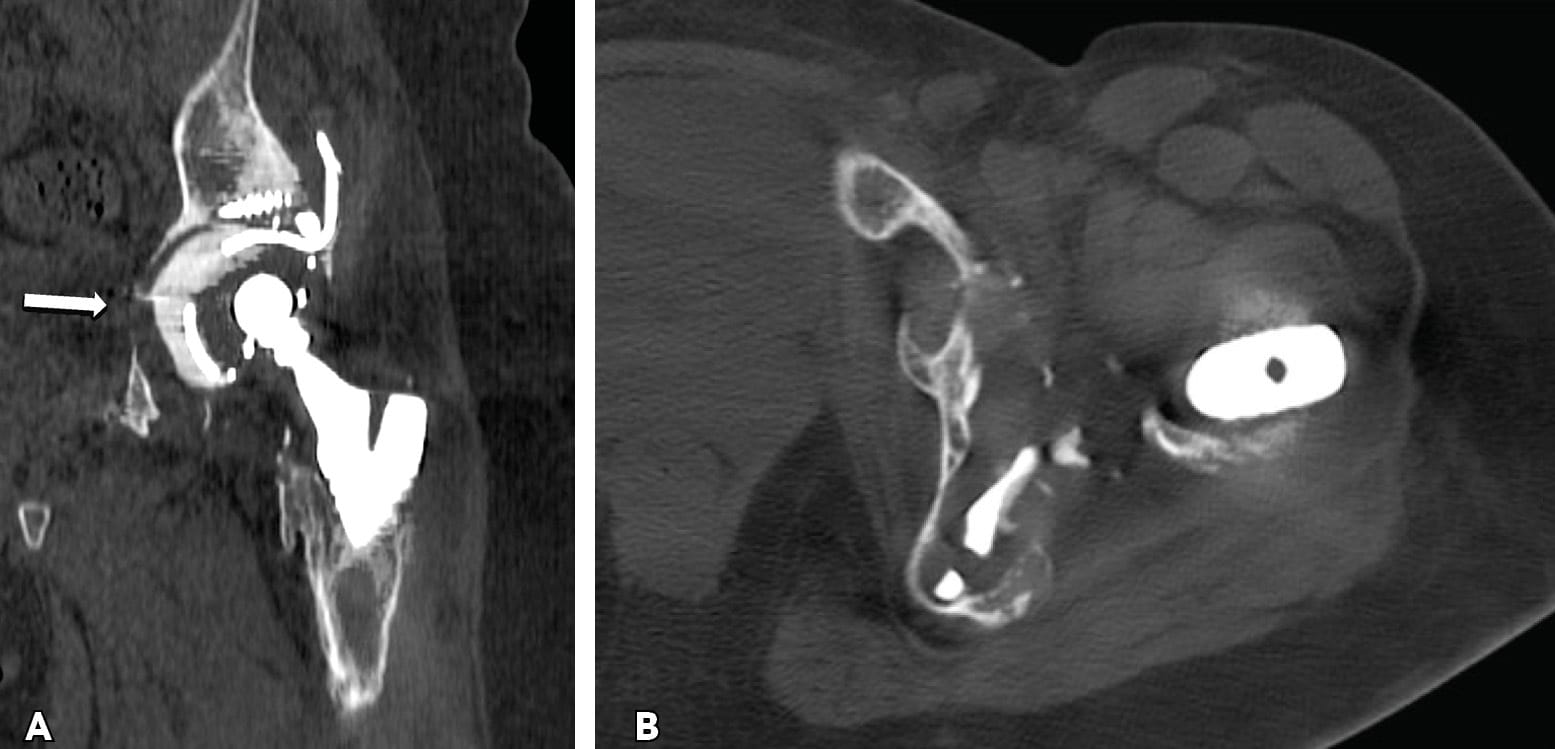

Conventional anteroposterior and lateral radiographs may initially be used for pre-operative planning for both post-traumatic and post-arthroplasty severe bone defects. PD should be suspected in cases with excessive osteolysis or fracture. When Kohler’s line and the tear drop is violated, and if moderate to severe ischial lysis is observed, and the cup and femoral head have migrated vertically more than 3 cm, one can safely suspect PD.[4], Paprosky WG, Perona PG, Lawrence JM. Acetabular defect classification and surgical reconstruction in revision arthroplasty. A 6 year follow up evaluation. J Arthroplasty. 1994;9(1)33-34.[5] Sporer SM, Paprosky WG. Acetabular revision using a trabecular metal acetabular component for severe acetabular bone loss associated with pelvic discontinuity. J Arthroplasty. 2006; 21(6)(S):87-90. However, the diagnosis of both post-traumatic malunion or nonunion and the diagnosis of PD in standard imaging views are difficult due to the fact that the implants obstruct full visibility of bone defects, especially when the posterior column is involved.[2], Schwarzkopf R, Ihn HE, Ries MD. Pelvic discontinuity: modern techniques and outcomes for treating pelvic disassociation. Hip Int. 2015; 25(4):368-74.[3] Babis GC, Nikolaou VS. Pelvic discontinuity: a challenge to overcome. EFORT Open Rev. 2021; 6(6):459-471. The use of a helical CT-scan and, more recently, the use of CT-scan thin slices in three planes, in combination with metal artifact reduction techniques, have improved diagnostic accuracy (Figure 2).[6], PuriL, Wixson RL, Stern SH, Kohli J, Hendrix RW, Stulberg SD. Use of helical computed tomography for the assessment of acetabular osteolysis after total hipa arthroplasty. J Bone J Joint Surg Am. 2002; 84(4):609-614.[7] Wellenberg RHH, Hakvoort ET, Slump CH, Boosma MF, MAAs M, Streekstra GJ. Metal artifact reduction techniques in musculoskeletal imaging. Eyr J Radiol. 2018; 107:60-69. Occasionally, a pre-operative CT angiogram is performed, when the removal of an intra-pelvic acetabular cup is planned. Despite technological improvements, one has to understand that resulting bone loss is usually greater than that which is initially anticipated during pre-operative planning.

Triflange and tumour like custom made acetabular impants. Modern technology allows the production of personalised implants for special conditions. These type of implants are custom made, porous coated titanium implants and are considered the last therapeutic salvage option, before excisional arthroplasty, for severe acetabular defects and PD. The implants are designed and manufactured based on pelvic models created by thin-slice pelvic 3-D CT-scans with metal subtraction software (Figures 7 and 8). Early and mid-term outcomes are encouraging but premium cost and length of production time limit their use.[20], DeBoer DK, Christie MJ, Brinson MF, Morrison JC. Revision total hip arthroplasty for pelvic discontinuity. J Bone Joint Surg Am. 2007; 89(4):870-876.[21], Taunton MJ, Ferhing TK, Edwards P, Bersasek T, Holt GE, Christie MJ. Pelvic discontinuity treated with custom triflange component: a reliable option. Clin Orthop Relat res. 2012; 470(2):428-434.[22] Zhang Y, Gao Z, Zhang B, Du Y, Ma H, Tang Y, Liu Y, Zhou Y. The application of custom-made 3D-printed titanium augments designed through surgical simulation for severe bone defects in complex revision total hip arthroplasty. J Orthop Traumatol. 2022; 6:23(1):37.

Concerns for the use of custom made implants are related to the accuracy of the image based technique used for their production, the accuracy of the implant 3D fitting and implantation, the appropriate surgical approach and exposure and the manufacturing and biology of the implant-bone interface.[23], Hothi H, Henckel J, Bergiers S, Di Laura A, Schlueter-Brust K, Hart A. The analysis of defects in custom 3D-printed acetabular cups: A comparative study of commercially available implants from six manufacturers. J Orthop Res. 2023; 41(7):1505-1516.[24], Di Laura A, Henckel J, Wescott R, Hothi H, Hart AJ. The effect of metal artefact on the design of custom 3D printed acetabular implants. 3D Print Med. 2020; 26:6(1):23. [25] Gruber MS, Jesenko M, Burghuber J, Hochreiter J, Ritschl P, Ortmaier R. Functional and radiological outcomes after treatment with custom-made acetabular components in patients with Paprosky type 3 acetabular defects: short-term results. BMC Musculoskelet Disord. 2020; 10:21(1):835.